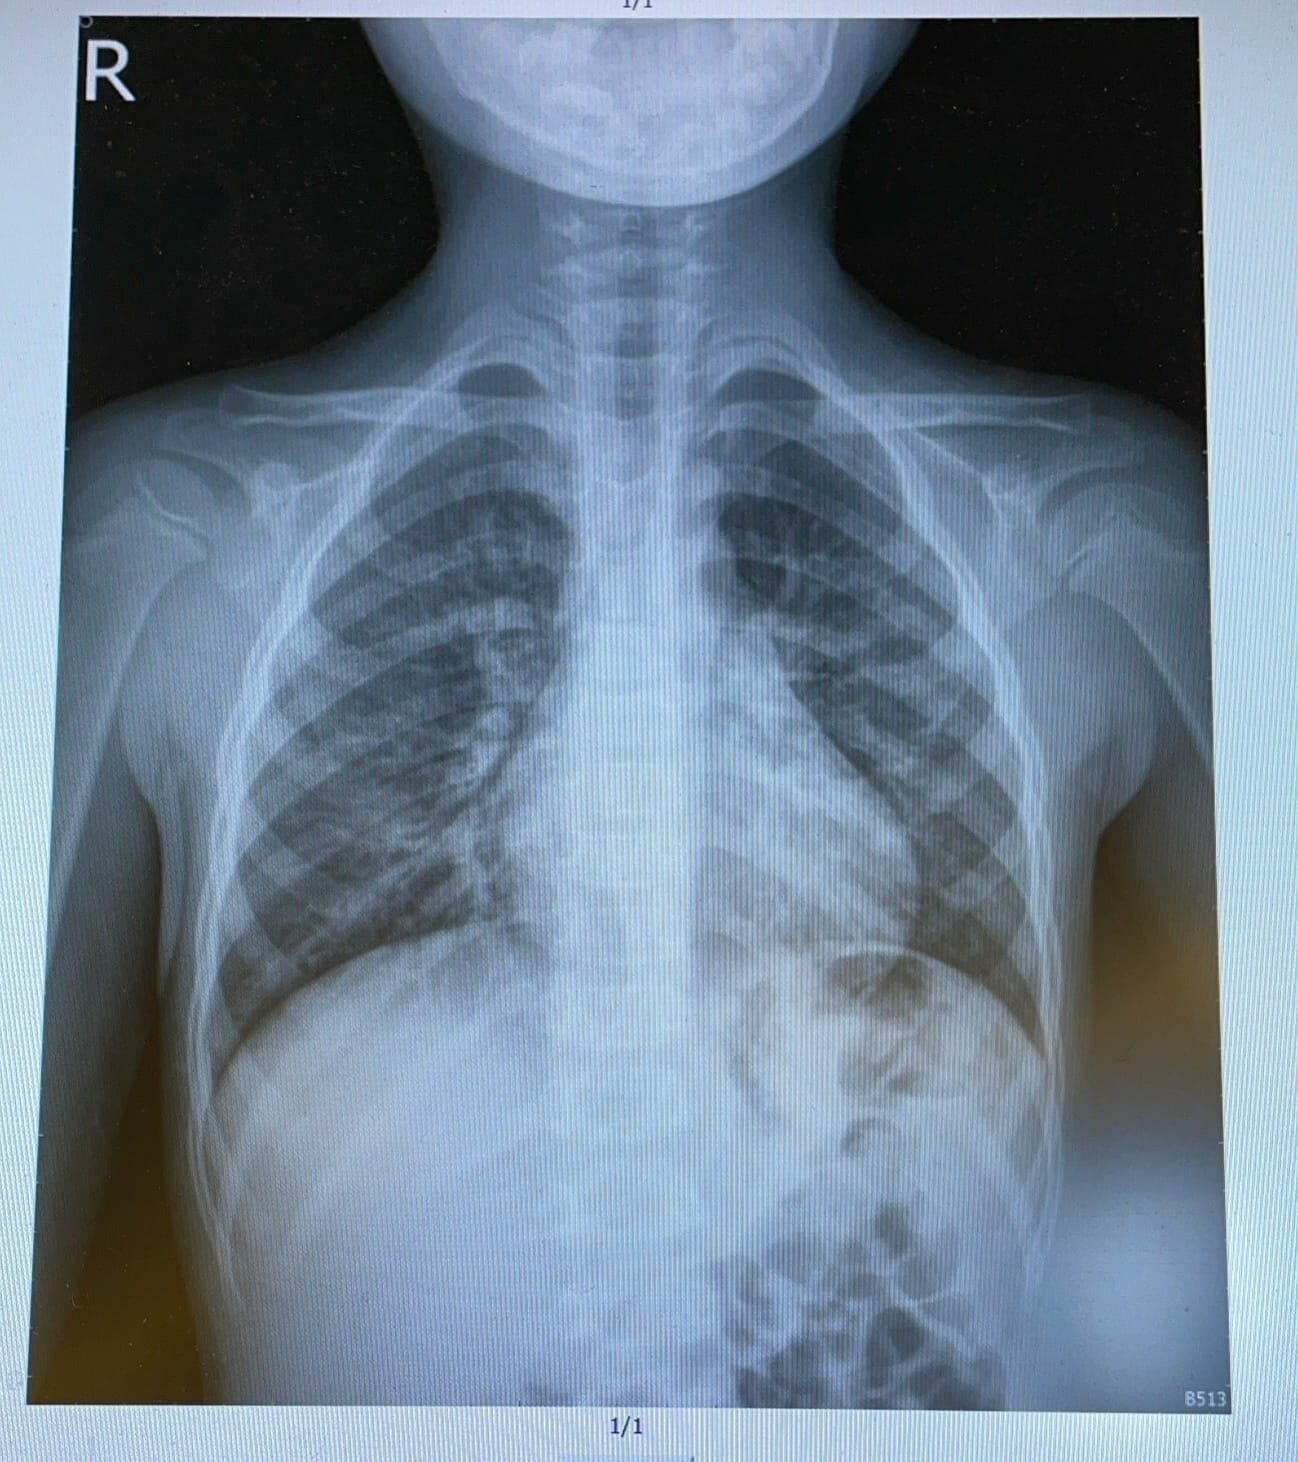

เมื่อวันที่ 5 ของอาการป่วย พ่อแม่จึงพาลูกไปตรวจสุขภาพที่โรงพยาบาล ตามรายงาน ผลการเอกซเรย์แสดงให้เห็นถึงปอดบวมและหลักฐานทางจุลชีววิทยา คือ ฮิวแมนเมตานิวโมไวรัส (Human Interstitial Pneumonia Virus : hMPV)